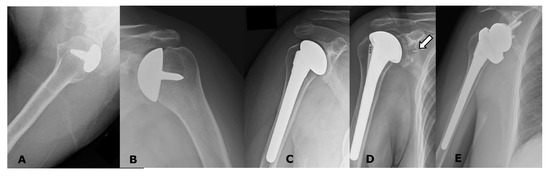

5.1. Anatomic Arthroplasties

5.1.1. Humeral Head Resurfacing/Stemless Hemiarthroplasty (HHRA)

5.1.2. Hemiarthroplasty (HA)

5.1.3. Anatomic Total Shoulder Arthroplasty (ATSA)

5.2. Reverse Arthroplasty

Reverse Total Shoulder Arthroplasty (RTSA)